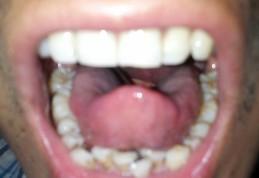

肉眼看的会厌图片

肉眼看的会厌图片,舌根会厌图片

张开嘴看到的会厌图片

张嘴能看到会厌

伸舌头看到会厌图片

看到会厌